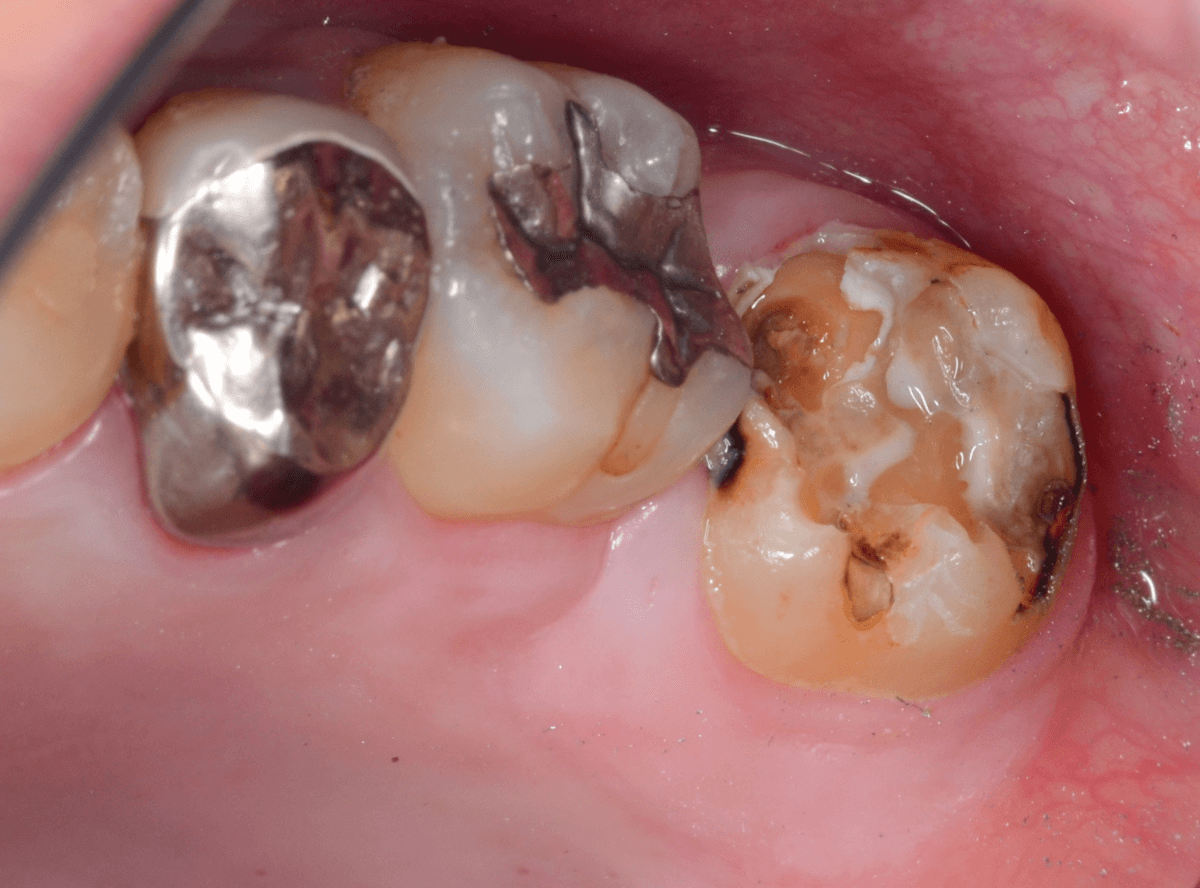

Case.14 インレーの下の歯肉まで広がった虫歯

「下の奥歯が噛むと痛む」という症状で来院された患者さんのケースです。

お口の中の状態を確認すると、奥歯の端に穴が開いているのが見えます。

ここかな?

やはり、奥歯の端が大きな虫歯になっています。

中のお薬も慎重に外して虫歯を除去します。

虫歯が深く、歯肉の下まで浸食していましたので、歯肉を部分切除し、虫歯を全て除去したところで、奇跡的に神経スレスレの状態でとどまっていました。

何とも言えませんが、神経を残せる可能性が出てきました。

虫歯が神経まで達していなくても、治療前から自発痛(何もしなくても痛い)があれば、神経をとらなければいけません。

今回は、そこまでの症状がありませんでしたので、患者さんと相談の上、神経を取らずに残す方法で様子を見る事になりました。

痛みが出ませんように。。。